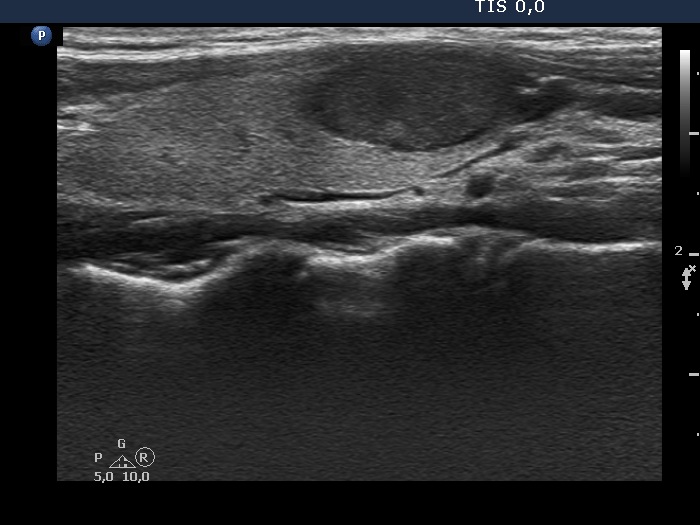

Second examination 3 years later (second row of images)

Clinical data: The patient had no complaints.

Palpation: unchanged.

Laboratory test: TSH 0.79 mIU/L.

Ultrasonography. Both the pattern and the size of the nodule in the right lobe remained unchanged. The cystic content of the left lobule has disappeared, it was replaced by inhomogeneous solid part. The vascularization of this lesion has also changed, the intranodular vascularization has become significantly increased.

Suggestion ultrasound in three years.